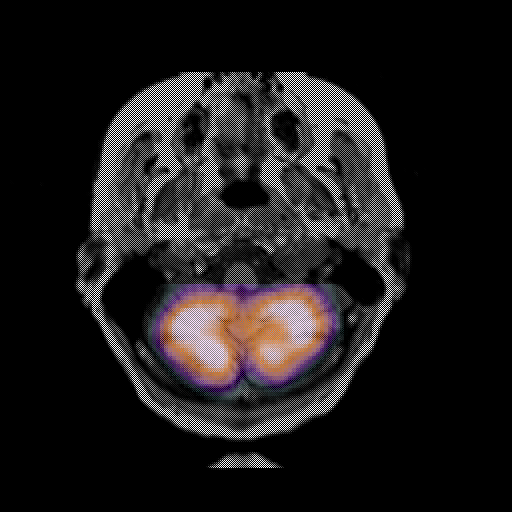

overlay: Slice 8

Slice 8

MRCBFCBF with

T1PDT2T1PDT2